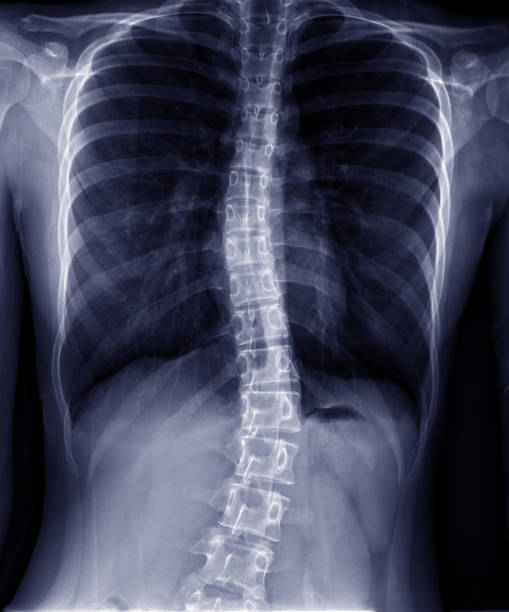

척추 측만증은 척추의 곡선이 비정상적으로 증가하여 등이 한쪽으로 치우치는 질환 입니다.

이로 인해 등이 비대칭적으로 변형되며 체형이 휘어지게 되는데요.

척추 측만증은 통증과 불편감을 유발할 뿐만 아니라 심각한 경우에는 신경 손상과 호흡 기능 저하를 초래할 수 있습니다.